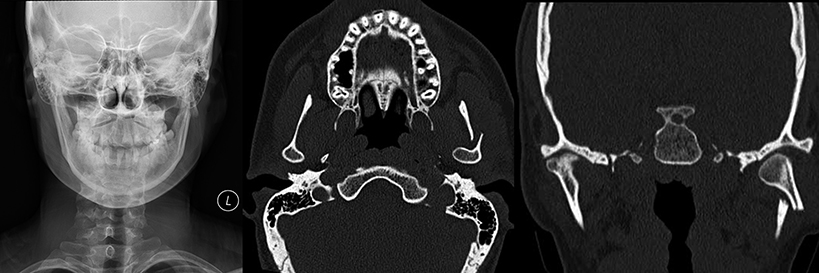

Neuroradiologists interpret MRI, CT, Myelograms, PET Scans and Nuclear Medicine studies of the brain, spine, neck, face, TMJ, orbits, head and temporal bones.

• Temporomandibular joint (TMJ) (using MR imaging)